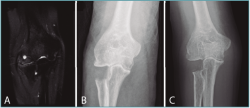

En casos de patología degenerativa, bien sean de causa postraumática o reumatoide, la combinación de sinovectomía y liberación articular con resección de la cabeza radial ha obtenido buenos resultados (Figura 2)(1). Se trata de casos con deformidad de la cabeza radial y cambios degenerativos con afectación importante de la articulación radiocapitelar, en los que una liberación mecánica mejora el dolor y el rango de movilidad. En estos casos, la opción terapéutica alternativa sería la prótesis de la cabeza radial o la artroplastia radiocapitelar. A la hora de tomar esta decisión, se deben tener en cuenta el dolor, la pérdida funcional y las limitaciones en las actividades de la vida diaria(1).

Figura 2. Caso de artrosis de codo. Se trata de un paciente de 58 años con artrosis de codo de predominio radiocapitelar que se aprecia en el corte coronal de la resonancia magnética (A). Se realizó una capitectomía artroscópica sin complicaciones (B). Cinco años tras la capitectomía (C) se aprecia conservación de la articulación humerocubital sin pinzamiento lateral.